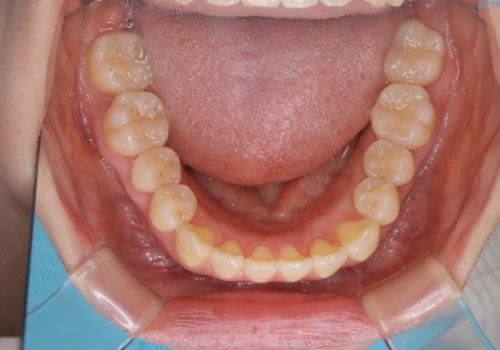

- 前歯のがたつきが気になるとご相談にいらした方です。右側前歯部のクロスバイトの他、左側にもシザーズバイトが認められたため、インビザラインにて治療を行いました。出産直後のため、ご自身の時間がなかなか取れないとの事で、最小限の来院回数で治療を勧められるように計画しました。

患者様ご自身で使用時間をしっかり管理して頂くことを条件に、最低限の来院回数で治療を進めていきました。20時間以上の使用を厳守して頂けたことで、少ない来院回数にて治療を終了することが出来ました。前よりも噛みやすくなったと大変喜んでいただけました。